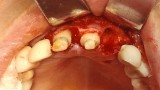

Bogata w płytki i leukocyty fibryna jest stosowana w regeneracji tkanek od ponad 15 lat. Pozytywny wpływ PRF (platelet-rich fibrin) na regenerację tkanek miękkich jest niewątpliwy, bezsporny i częściowo udowodniony w badaniach klinicznych i analizach biochemicznych. Wpływ PRF na regenerację tkanki kostnej jest obserwowany klinicznie, ale nadal niedostatecznie poznany jest mechanizm tego zjawiska.

Platelet- and leukocyte-rich-fibrin has been used in regeneration of tissue for more than 15 years. The positive influence of PRF on the regeneration of soft tissue is undoubtedly, without question and partially proven in clinical studies and biochemical analysis. Influence of PRF on regeneration of bone tissue is observed clinically but the mechanism of this phenomenon is still not sufficiently known.